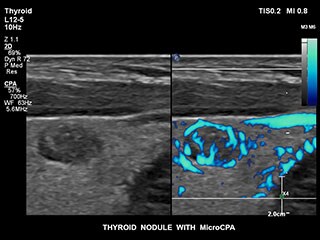

Obtaining flow information in small low-flow vascular structures has traditionally been a challenge. With EPIQ’s new MicroCPA feature, visualization of low velocity micro circulation is quick and simple, giving you more diagnostic confidence when evaluating organ perfusion or small vascular beds.